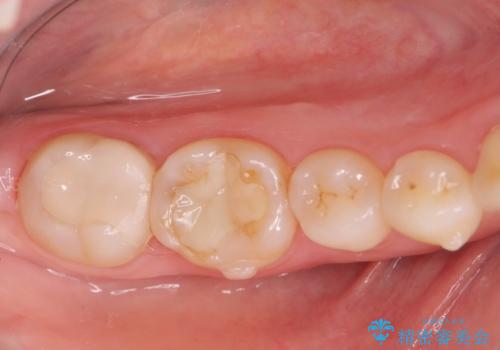

- 徐々に大きくなってきた骨隆起の除去を希望され来院されました。

下顎隆起を切除することで舌を収めるスペースを確保し発音のしやすさの向上を図ります。